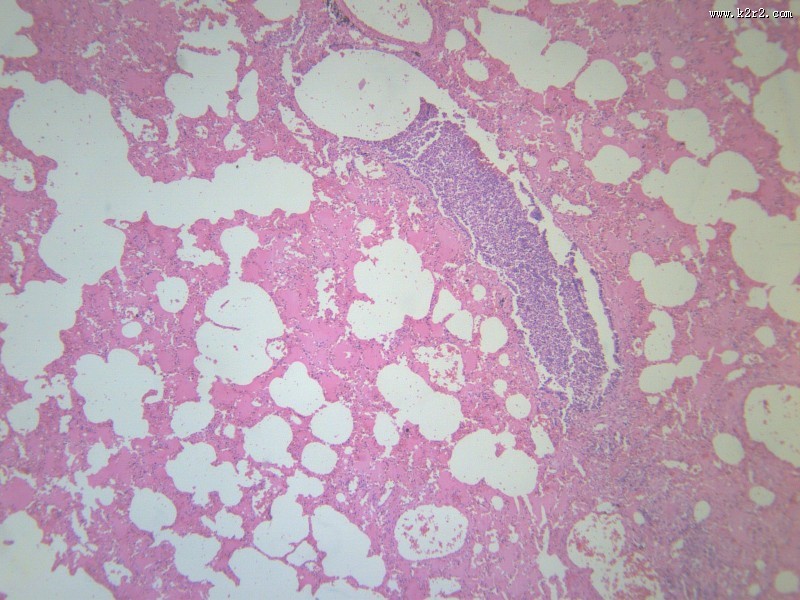

小叶性肺炎 - 第8张

小叶性肺炎

医学

显微切片

炎症

肺炎

bronchopneumonia

支气管肺炎